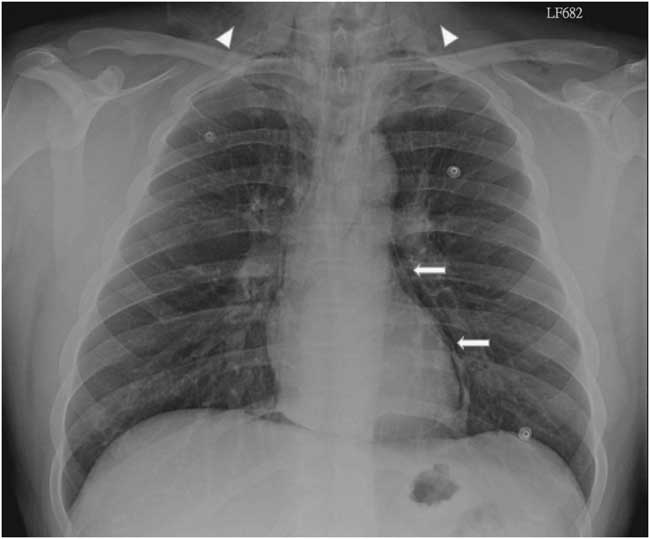

A 22-year-old male presented to the emergency department due to progressive odynophagia and dysphagia. He underwent a left third mandibular molar extraction at the dental clinic a week prior. At the emergency department, vital signs were normal except tachycardia (114/min) and tachypnea (22/min). A physical examination revealed bilateral neck tenderness with crepitus on palpation, no stridor or acute airway compromise signs. Laboratory data showed leukocytosis (white blood cell count, 19000/cumm; segmented, 91%) and elevated C-reactive protein (1.07 mg/dL). Radiographs showed the presence of prevertebral emphysema on the C-spine lateral view (Figure 1) and subcutaneous emphysema with pneumomediastinum on the chest posteroanterior view (Figure 2). A non-contrast computed tomography (CT) scan confirmed the radiographic findings; additionally, there was gas collection over the pericarotid, pericardial (Figure 3) and extradural spaces (Figure 4). Because there was no CT evidence of infectious signs and clinical features were stable, conservative treatment with intravenous amoxicillin/clavulanic acid was given for a week. Clinical symptoms improved, and a follow-up CT showed no residual gas.

Figure 2 Posteroanterior chest radiograph shows subcutaneous emphysema (arrow heads) and pneumomediastinum (arrows).